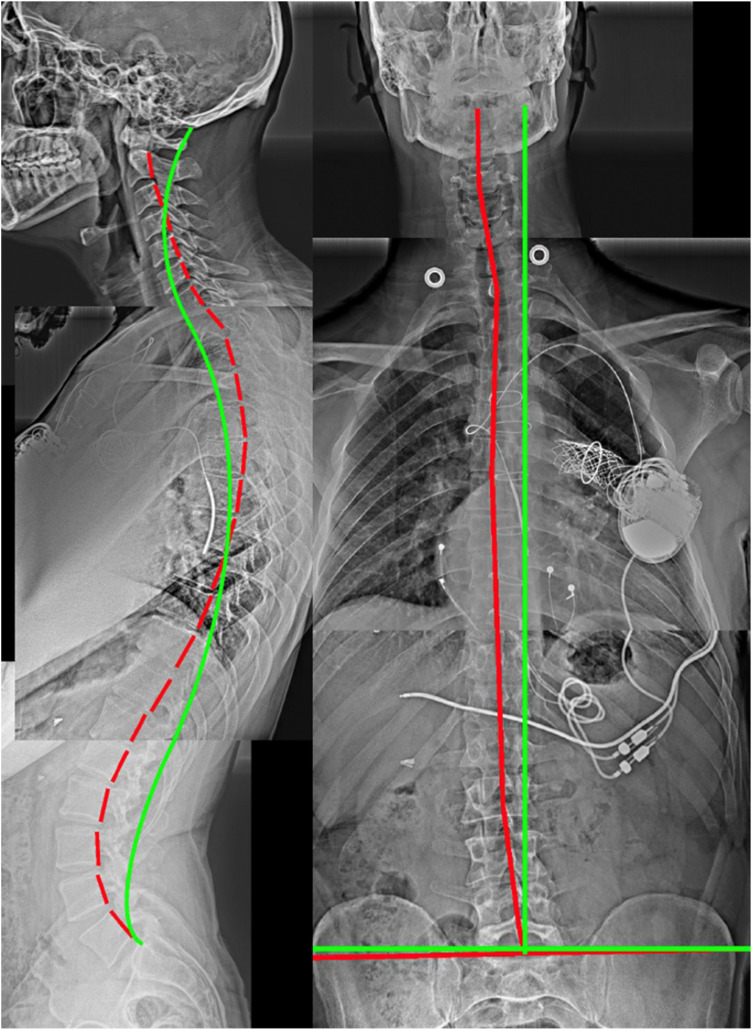

Postural alignment is a critical determinant of health status. Its degradation is associated with deformity-caused and compensation-related back pain, neurologic involvement, osteoarthritic development, as well as disability and reduced quality of life. Radiography remains the most efficient method of evaluating standard sagittal and coronal spine and pelvic metrics that are used to plan surgical and nonsurgical treatment strategies. Many current spine guidelines dissuade the use of initial screening X-rays and some chiropractic guidelines condemn repeat imaging to assess progress from treatment regimens; these are anti-scientific viewpoints that ignore alternate viewpoints and evidence. Current understanding of the relationship between different spinopelvic parameters are essential to plan biomechanically appropriate interventions that are patient-specific. There are radiographically measured parameter thresholds critically related to several spinal disorders and positive patient outcomes. Current guidelines must include a caveat for contemporary biomechanical evaluation and its consequent specific treatments and should recommend routine radiographic imaging for spine patients undergoing corrective rehabilitative interventions. The failure to radiographically diagnose spinal deformity is argued to be negligence in many cases. The prime obstacle to routine X-ray imaging lies with the presumed threat of cancer, however, this is dogma; we summarize the main evidence from recent publications why this is so.

Abstract Image